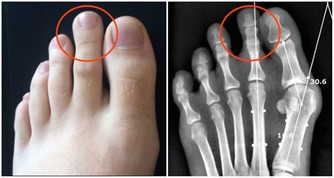

2.愛滋病的傳播途徑?愛滋病的傳播途徑分別是性傳播、血液傳播、母嬰傳播。目前性傳播是最主要的傳播方式。